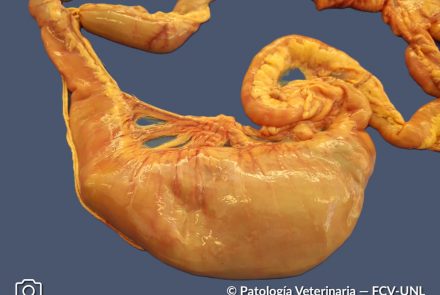

Obstrucción intestinal por cuerpo extraño – Contenido alimentario compacto

En el duodeno se observa una marcada dilatación de la luz intestinal debido a la presencia de una colecta voluminosa de material vegetal (pasto) y restos

óseos compatibles con huesos de pollo. El contenido intestinal hacia el segmento distal es exclusivamente líquido, lo que sugiere una obstrucción

intestinal mecánica parcial o completa.

Especie: Canino